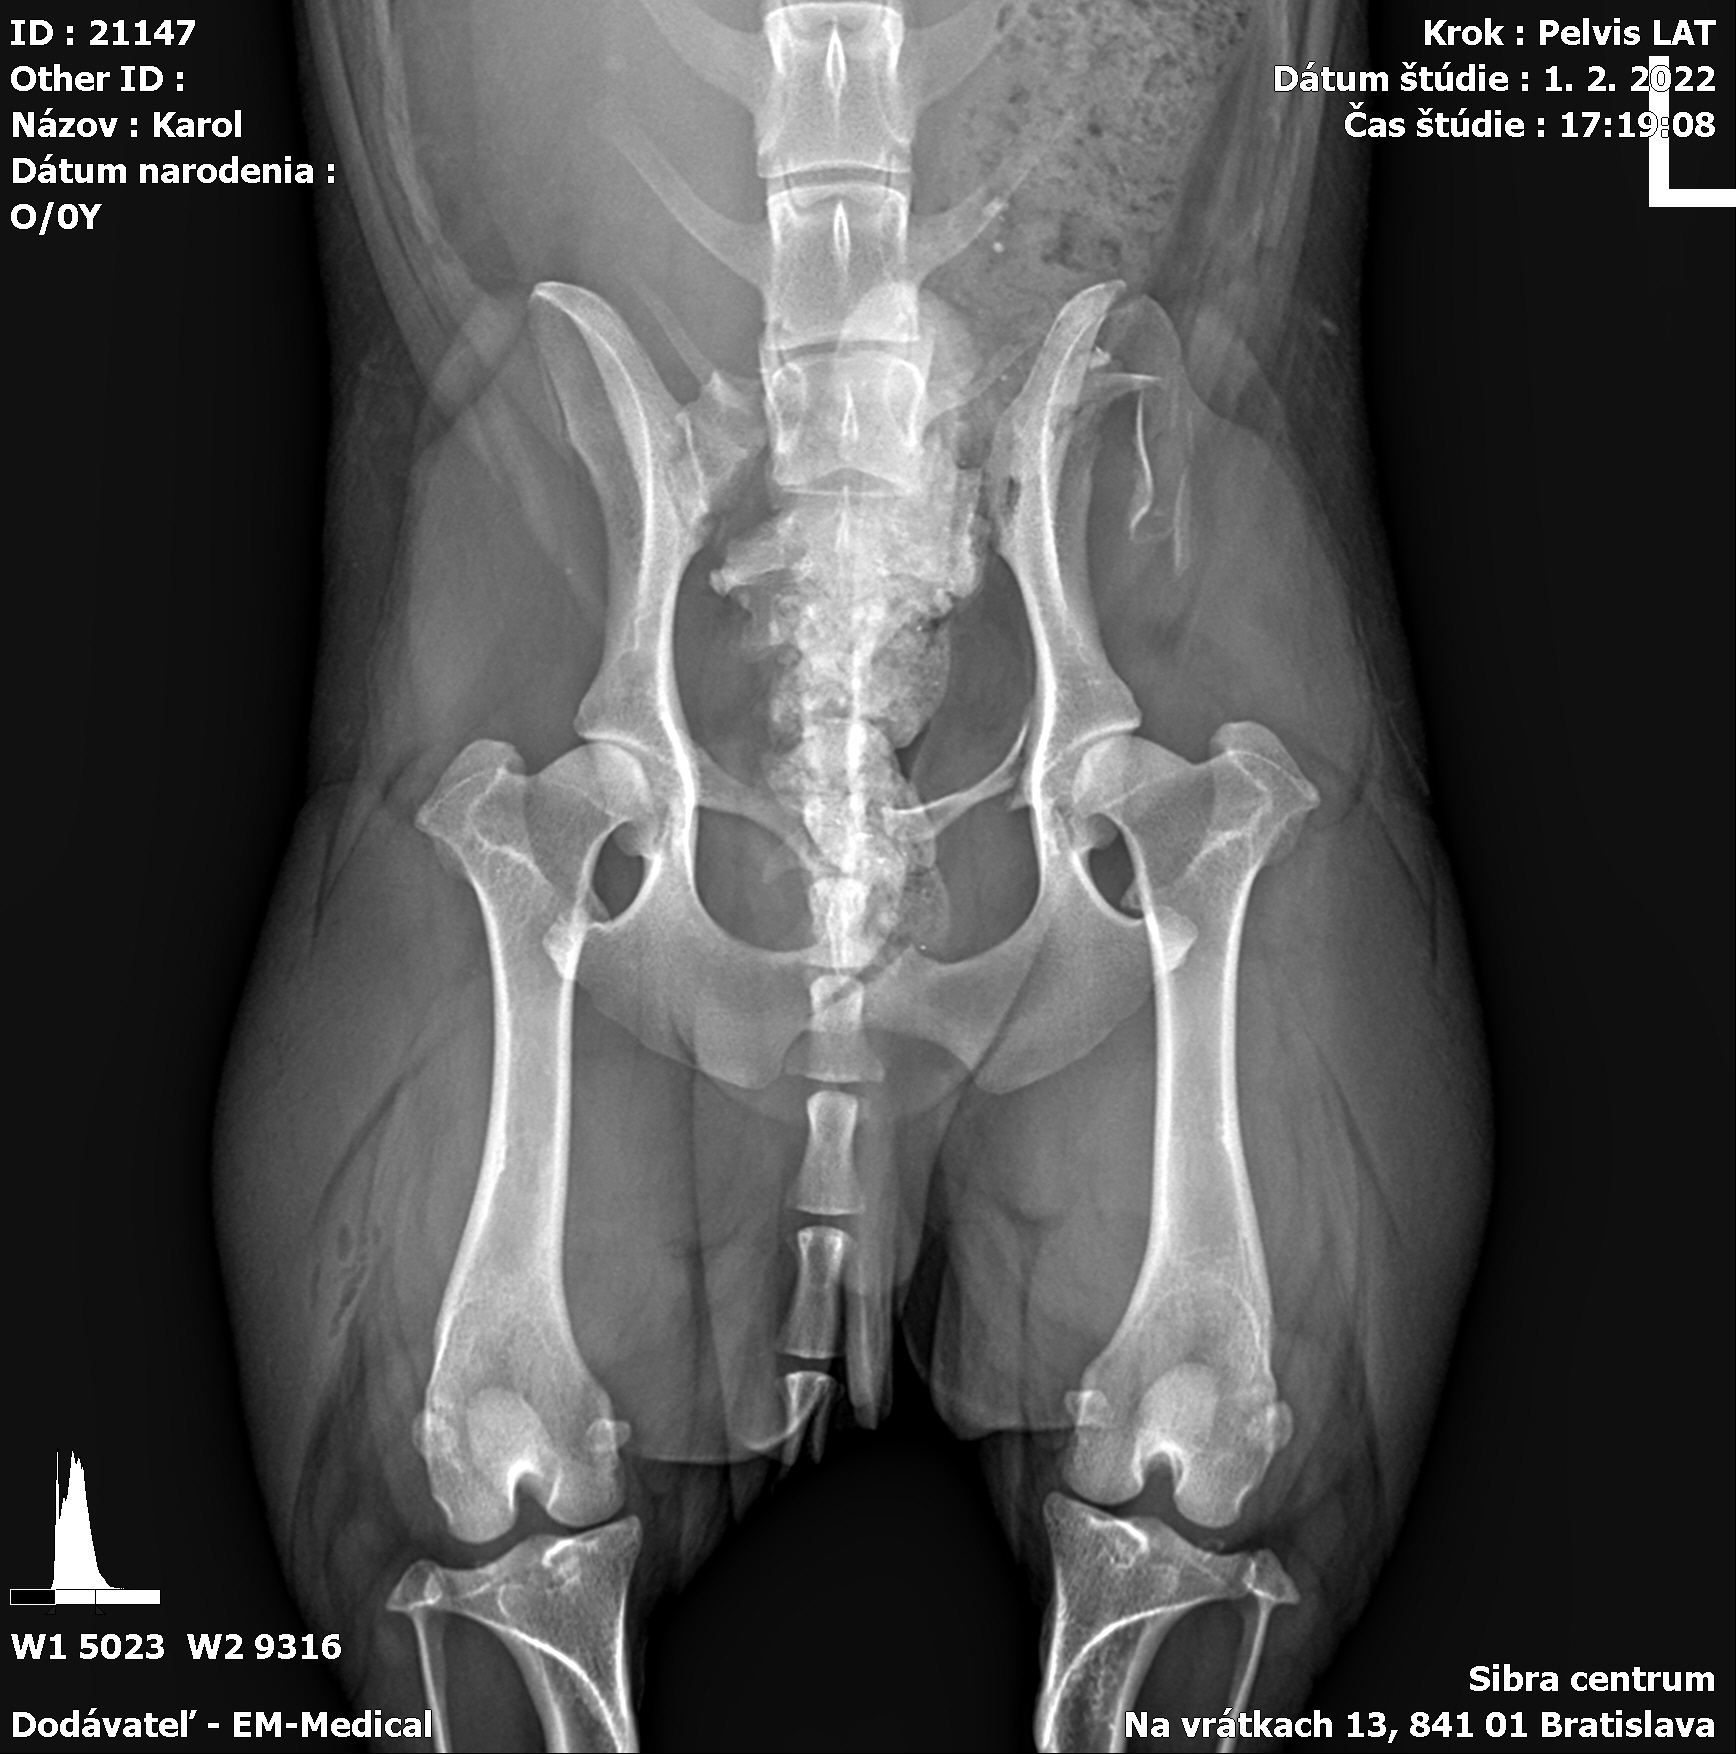

Karola nám doviezla pani, ktorá ho našla, asi jediná dobrá duša, ktorá pri ňom neprešla so zatvorenými očami. Ihneď sme s krpcom utekali na veterinu aby sa zistila závažnosť jeho zranení. Hneď pri prvých RTG snímkoch sa ukázala obojstranná fraktúra panvy, taktiež fraktúra krídla panvy a keby mu to chudákovi nestačilo, do tretice sa objavila zlomenina stavca. Karolko mal neznesiteľné bolesti, ale krásne prečkal vyšetrenie lebo vedel, že je v dobrých rukách a dostáva sa mu pomoci. Po nálezoch sme okamžite kontaktovali neurológiu a ortopédiu na veterinárnej klinike Sibra - centrum veterinárnej medicíny, kde sme dostali hneď termín na príjem.

Karol nemá žiadne neurologické deficity, po ortopedickej operácii bude vedieť behať a bez problémov bude vedieť samostatne cikať a kakať. Po tejto úžasnej správe sme samozrejme dali zelenú náročnej ortopedickej operácii pod vedením MVDr. Vatolíka. Operácia sa podarila na výbornú, Karči je "zoskrutkovaný" a vôbec nič mu nebráni v tom, aby opäť mohol behať a aktívne žiť. Momentálne sa zotavuje po operácii, musí mať prísny kľudový režim. Po vybratí stehov ho čaká hydro- a fyzioterapia, ktorá mu pomôže postaviť sa na nohy. Je to bojovník, veľmi sa chce uzdraviť a v jeho očkách je dokonale vidieť, že už kuje plány čo všetko zameškané bude musieť dobehnúť.